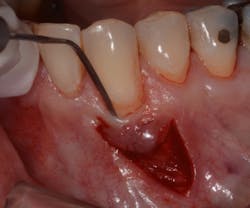

The Bernotti V-Y Flap involves making a submarginal supraperiosteal V-shaped incision 1 mm to 2 mm apical to the mucogingival junction, creating a pedicle flap (figures 2 and 2a). This flap is extended one tooth mesially and distally to the recession defect. It is important to note that the flap should leave the adjacent papillae intact in order to preserve blood supply. An intrasulcular incision is then made with a microsurgical blade to allow for coronal movement of the marginal tissue without tension (figure 3). The root is then scaled/root planed and chemically modified with an amoxicillin slurry for three minutes (figure 3a).